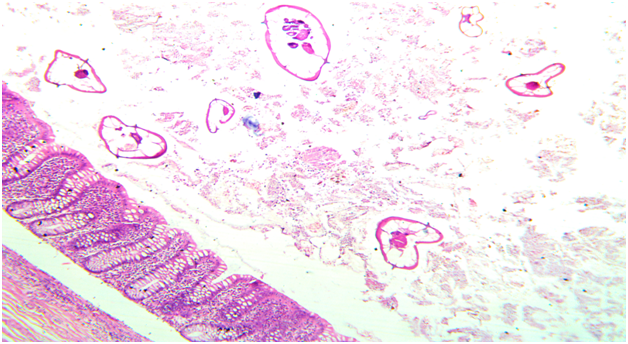

Figure 1 Microscopic photo showing mucosa of appendix with lumen showing multiple enterobious vermicularis parasite. (HE, X10)

A 22 year old male patient came to the casualty department with pain in abdomen. On physical examination there was right iliac fossa tenderness. A laboratory investigation revealed a normal Complete Blood Count (CBC). Serum immunoglobulins levels were not done in this patient as clinicians did not suspect parasitic infection as a cause of acute appendicitis.Ultrasonography was performed and did not show inflammation of appendix or any other abdominal organ. Clinical diagnosis of acute appendicitis with unkown etiology was made and patient underwent open appendicectomy. The specimen was sent for histopathological examination to know the exact cause of appendicitis. On gross examination appendix appeared normal with presence of fecolith. Microscopic examination revealed mucosa with inflammatory infiltrate predominantly comprising of eosinophils which is most commonly seen in parasitic infection and lumen showed parasite of Enterobius Vermicularis (Figure 1&2). The rest of the layer submucosa, muscle layer and serosa appeared normal and showed no evidence of neutrophilic infiltrate or congested blood vessels which is usually is seen in acute appendicitis without parasitic infection. (Figure 3). The diagnosis of acute appendicitis secondary to Enterobius Vermicularis infection was given. Post operatively a dose of mebendazole 100mg was given and patient is being followed up.